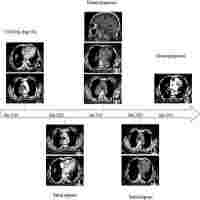

| Abstract | Background: As angiogenesis is an essential step in tumor growth and metastasis, the tyrosine kinase inhibitor (TKI) apatinib has become a revolutionary anticancer therapy across various malignancies. However, its efficiency and safety in Merkel cell carcinoma (MCC) are uncertain. Case presentation: The current study described the case of a 91-year-old man who presented with a 3.2×3.0×2.2 cm rapidly growing, solitary tumor of the right lower eyelid. It was diagnosed as MCC pathologically. Twenty-seven days after the surgery, the patient returned to the hospital with recurrent MCC. Apatinib was then administered to this patient. The patient had a complete response (CR) to apatinib after 4.4 months of targeted therapy. Twenty-seven months of progression-free survival (PFS) was achieved with controllable treatment-related adverse events (AEs). Conclusion: Treatment with apatinib demonstrated clinical benefit in our patient with recurrent MCC, highlighting its potential utility in other MCC patients. Further clinical trials are needed to determine the efficacy and safety of apatinib in MCC patients. |